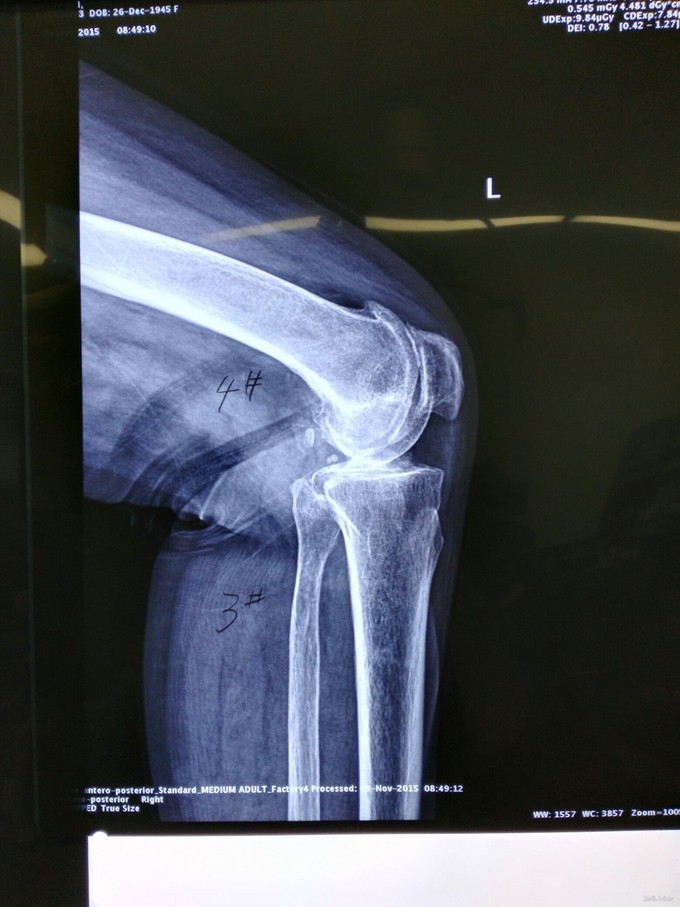

患者老年女性,68岁 主诉:双膝关节疼痛30年,加重2年 现病史:患者30年前无明显诱因间断出现双膝关节疼痛,为针扎样痛,无明显放射,休息、制动后可缓解,天气寒冷时疼痛有所加重,不伴弹响、僵直,不伴发热、盗汗。未规律诊治。2年前双膝疼痛再次加重,保守治疗无效。 既往史:诊断高血压病5年,最高150/90mmHg,规律服药,血压控制可。

查体:步入病房,步态基本正常,双侧膝关节外翻畸形,无屈曲畸形,四肢肌容量肌张力正常。 辅助检查:见图

诊断:双膝严重骨关节炎 治疗:双侧人工膝关节置换术

随诊:患者手术顺利,恢复良好 讨论:骨性关节炎是一种慢性关节疾病,它的主要改变是关节软骨面的退行性变和继发性的骨质增生。主要表现是关节疼痛和活动不灵活,X线表现关节间隙变窄,软骨下骨质致密,骨小梁断裂,有硬化和囊性变。关节边缘有唇样增生。后期骨端变形,关节面凹凸不平。关节内软骨剥落,骨质碎裂进入关节,形成关节内游离体,实际并非炎症,主要为退行性变,属关节提前老化,特别是关节软骨的老化。骨性关节炎代表着关节的衰老,故称之为老年性关节炎。